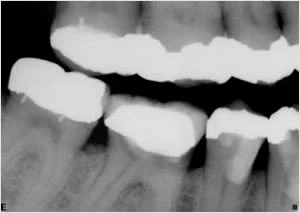

Bệnh nhân tới phòng khám của tôi và được thực hiện thủ thuật điều trị tiêu chuẩn bao gồm các răng đã được làm chụp phải có phim cánh cắn để đánh giá tình trạng và chất lượng đường viền phục hình mặt bên.

Phim cận chóp ban đầu cho thấy đường viền phía gần của răng không đồng đều. Vì tấm phim được chụp không sử dụng cây định hướng tia nên tôi nói với trợ lý của mình tôi cảm thấy hình ảnh trên tấm phim này vẫn hơi ngắn.Sau khi sử dụng phim cánh cắn (Hình 2) những nghi vấn của tôi đã được giải đáp. Bên dưới chụp răng có sâu lớn, xác định được bằng thăm khám trên miệng.

Hình 2: Phim cánh cắn của tôi.

Khi đó, tôi giải thích cho bệnh nhân điều tôi vừa phát hiện ra. Khi bệnh nhân vẫn ấn tượng rằng điều trị nội nha là điều trị thực hiện định kì và có thể thực hiện qua chụp đơn thuần, hiện tại chúng tôi lại có một tình huống hoàn toàn khác. Trường hợp này cần phải cắt chụp răng và tôi đã thông báo với bệnh nhân tôi nghi ngại răng này không thể phục hình được.